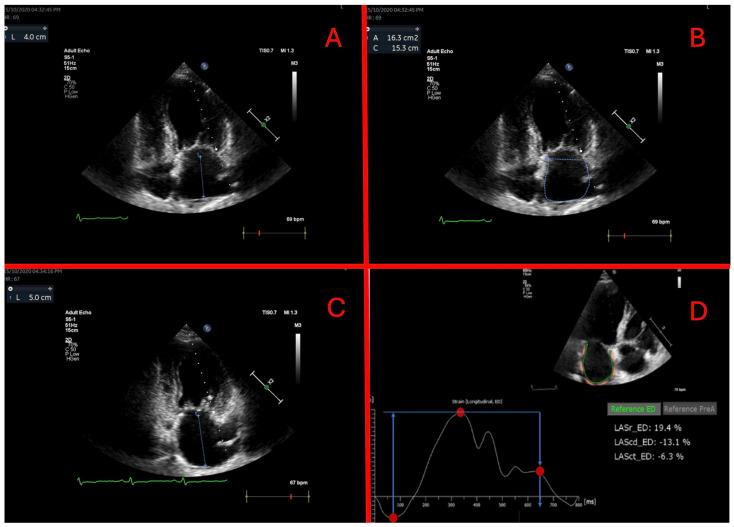

: Atrioventricular (AV) dyssynchrony as well as atrial and ventricular pacing affect left atrial (LA) function. We conducted a study evaluating the effect of atrial and ventricular pacing on LA morphological and functional changes after dual-chamber pacemaker implantation. : The study prospectively enrolled 121 subjects who had a dual-chamber pacemaker implanted due to sinus node disease (SND) or atrioventricular block (AVB). Subjects were divided into three groups based on indication and pacemaker programming: (1) SND DDDR 60; (2) AVB DDD 60 and (3) AVB DDD 40. Subjects were invited to one- and three-month follow-up visits. Three subsets based on pacing burden were analyzed: (1) high atrial (A) low ventricular (V); (2) high A, high V and (3) low A, high V. LA function was assessed from volumetric parameters and measured strains from echocardiography. : The high A, low V group consisted of 38 subjects; while high A, high V had 26 and low A, high V had 23. A significant decrease in reservoir and contractile LA strain parameters were only observed in the high A, low V pacing group after three months (reservoir 25.9 ± 10.3% vs. 21.1 ± 9.9%, = 0.003, contractile -14.0 ± 9.0% vs. -11.1 ± 7.8, = 0.018). While the re-established atrioventricular synchrony in the low A, high V group maintained reservoir LA strain at the baseline level after three months (21.4 ± 10.4% vs. 22.5 ± 10.4%, = 0.975); in the high A, high V group, a further trend to decrease was noted (20.3 ± 8.9% vs. 18.7 ± 8.3%, = 0.231). : High atrial pacing burden independently of atrioventricular dyssynchrony and ventricular pacing impairs LA functional and morphological parameters. Changes appear soon after pacemaker implantation and are maintained.

该研究前瞻性纳入了 121 例因窦性心动过缓(SND)或房室传导阻滞(AVB)而植入双腔起搏器的患者。根据适应证和起搏器程控,将患者分为三组:(1)SND DDDR 60;(2)AVB DDD 60;(3)AVB DDD 40。患者被邀请在 1 个月和 3 个月时进行随访。分析了基于起搏负担的三个亚组:(1)高心房(A)低心室(V);(2)高 A、高 V;(3)低 A、高 V。从容积参数和超声心动图测量的应变评估 LA 功能。

高 A、低 V 组有 38 例;高 A、高 V 组有 26 例,低 A、高 V 组有 23 例。仅在高 A、低 V 起搏组中,在 3 个月后观察到储备和收缩期 LA 应变参数显著下降(储备 25.9 ± 10.3%比 21.1 ± 9.9%, = 0.003,收缩-14.0 ± 9.0%比-11.1 ± 7.8%, = 0.018)。而在低 A、高 V 组中,重新建立的房室同步性在 3 个月后保持了储备 LA 应变的基线水平(21.4 ± 10.4%比 22.5 ± 10.4%, = 0.975);在高 A、高 V 组中,进一步下降的趋势明显(20.3 ± 8.9%比 18.7 ± 8.3%, = 0.231)。